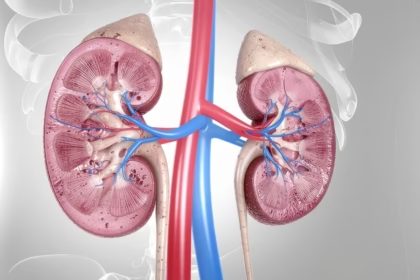

Akut Böbrek Yetmezliği (ABY) Nedir? Böbreklerin Filtreleme Dengesinin Bozulması

Bu içerikle, akut böbrek yetmezliğinin nasıl ortaya çıktığını, böbreklerin filtreleme sisteminin nasıl…